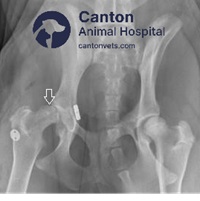

X-rays (radiographs) – Confirming hip dislocation and assessing joint damage.

Recheck X-rays are performed at follow-up visits to monitor implant positioning